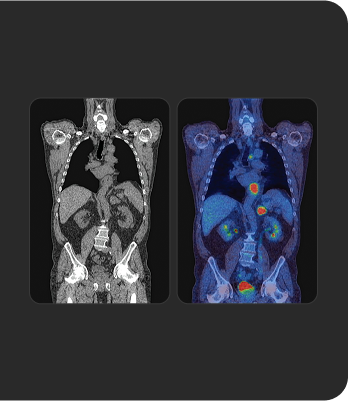

Tratar o que se vê

Os radioligandos podem ter uma finalidade e aplicação diagnóstica e terapêutica, permitindo uma abordagem teranóstica, que pode ser traduzida pela afirmação "tratar o que se vê e ver o se trata" (do inglês "see what you treat and treat what you see"). 1b 4 5